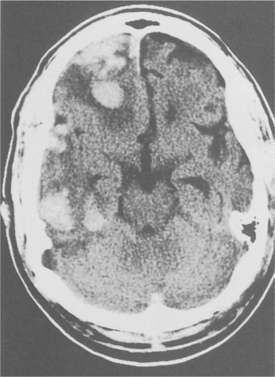

Diagnostic imaging can provide significant information, which can guide the intervention and allow a more accurate prognosis. CT is the primary imaging modality for the initial diagnosis and management of the head-injured person. CT scanning of the head reveals the presence of hemorrhage, swelling, or infarction. In individuals with traumatic coma, patterns on CT that have been associated with worse neurologic outcome include lesions in the brainstem, encroachment of the basal cisterns, and diffuse axonal injury (Fig. 33-7).51 An initially normal CT scan, however, is no assurance that hemorrhagic lesions will not occur.

Figure 33-7 CT scan of the head in a patient with a closed head injury. Severe compression of mesencephalic cisterns is seen, indicating midbrain compression. (Reprinted from Townsend CM: Sabiston textbook of surgery, ed 17, Philadelphia, 2004, Saunders.)

Diffuse axonal injury (DAI) is a frequent CT and pathologic correlate of severe TBI, accounting for about 50% of primary brain injuries. DAI is usually associated with a poor outcome. DAI is readily identifiable on CT as multiple punctate hemorrhages, typically in the deep white matter and corpus callosum and occasionally in the brainstem. DAI may also occur as a result of mild TBI and may culminate in subtle types of cognitive deficits. Approximately 10% to 15% of individuals with clinically severe TBI have a normal CT scan. In such situations, the possibility of extracranial or intracranial vascular disruptions may exist, and angiography should be considered.18